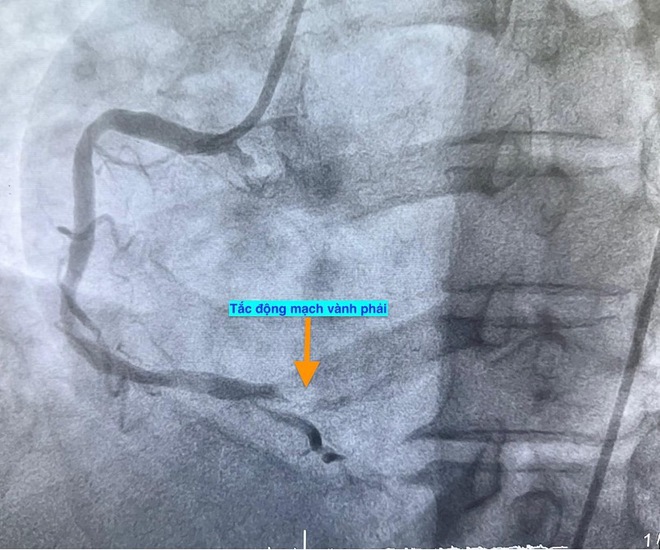

Trường hợp thứ ba, lúc 15 giờ 53 phút, nam bệnh nhân 78 tuổi nhập viện vì đau ngực. Bệnh nhân cho biết đau ngực từng cơn trong 3 ngày, ngày nhập viện thì đau ngực liên tục. Điện tim gợi ý nhồi máu cơ tim cấp; chụp mạch vành cấp cứu phát hiện bệnh nhân cũng tắc động mạch vành phải.

Hình ảnh chụp mạch vành cho thấy các bệnh nhân bị tắc mạch máu tim (do mảng xơ vữa, huyết khối) dẫn đến tình trạng thiếu máu cục bộ và nhồi máu cơ tim cấp